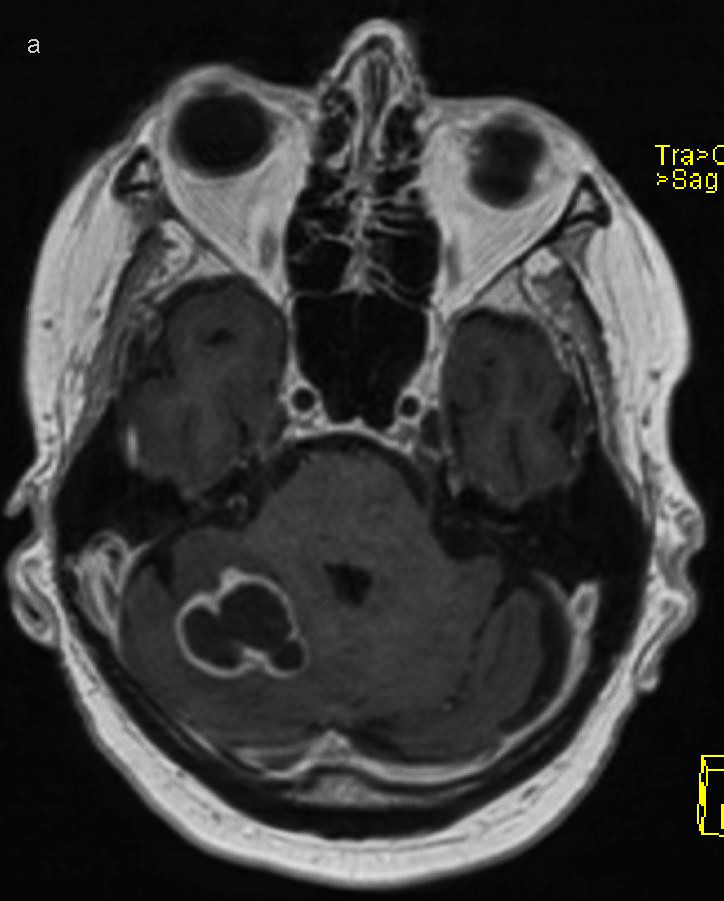

Seks uker etter oppstart av behandling for postkardiotomisyndrom og seks måneder etter aortaklaffoperasjonen, ble pasienten innlagt for niende gang som øyeblikkelig hjelp i medisinsk avdeling. I tillegg til tungpust, hevelser i bena og hjertebank som ved tidligere innleggelser hadde han frostfølelse og smerter i høyre legg og kne. Ved klinisk undersøkelse var han i redusert allmenntilstand. Han var afebril med normalt blodtrykk på 112/80 mm Hg, regelmessig puls på 104 slag/min og oksygenmetning på 95 % uten oksygentilførsel. Det var redusert respirasjonslyd basalt bilateralt som ved pleuravæske, gnidningslyd over prekordiet, lett hevelse i høyre kne og et reaksjonsløst arr etter sternotomi. Til forskjell fra tidligere innleggelser var inflammasjonsparametre betydelig forhøyet med leukocytter 18,2 × 109/L (3,5–10,0 × 109), CRP 224 mg/L (< 4,0) og SR 107 mm (< 12). CT thorax viste høyresidig pleuravæske med pleurareaksjon oppfattet som inflammasjon eller infeksjon, samt en mindre, abscessuspekt lesjon i høyre lunge (figur 1). På bakgrunn av det kliniske bildet og radiologisk mistanke om pneumoni med mulig empyem startet man empirisk behandling med cefotaksim 2 g × 3 for dekning av nosokomial etiologi. Nasofarynksprøve til bakteriedyrkning og PCR-tester for luftveispatogener, inkludert SARS-CoV-2, ga negative resultater.

Inokulasjon av Nocardia spp. ved åpen hjertekirurgi er ikke beskrevet i litteraturen. Fravær av lokal infeksjon i operasjonssted både klinisk og ved PET- og CT-undersøkelse, talte også imot dette hos vår pasient. Kontrastoppladning i pleura, pleuravæske og en abscessuspekt lesjon i lunge (figur 1) kunne skyldes både postkardiotomisyndrom og nokardiose, og det var utfordrende å skille inflammasjon fra infeksjon. Selv om vi aldri lyktes i å påvise mikroben i pleuravæske eller luftveier, antar vi at nedre luftveier var primærfokus, med videre hematogen spredning til hjerne og muskulatur i underekstremiteter.